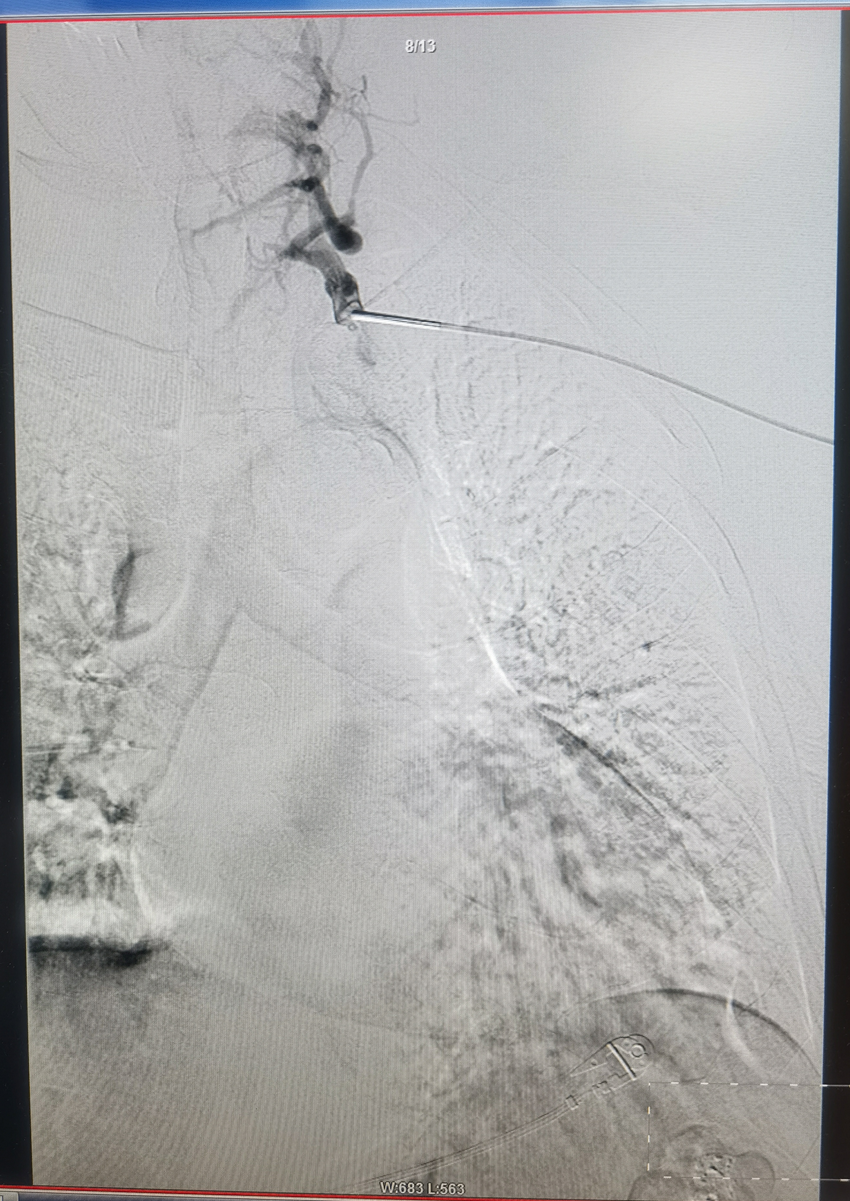

采用直径分别为6、8、10mm的球囊对闭塞段进行渐进性扩张,完成后造影显示左头臂静脉开通,左上肢的静脉血可以很顺畅的回流上腔静脉,动静脉瘘的压力明显降低。

这是我院周围血管病科完成的首例头臂静脉闭塞球囊扩张成形术,本病例充分体现了我科与其他兄弟科室通过MDT合作模式为患者排忧解难的合作精神,使患者在院内就能享受到优质医疗服务。